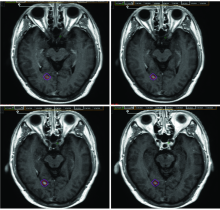

| [2] | 赵永瑞, 高莹, 陈怡东, 徐建堃. 基于直线加速器的分次立体定向放疗对小体积脑转移瘤的有效性及安全性[J]. 国际肿瘤学杂志, 2023, 50(3): 138-143. |